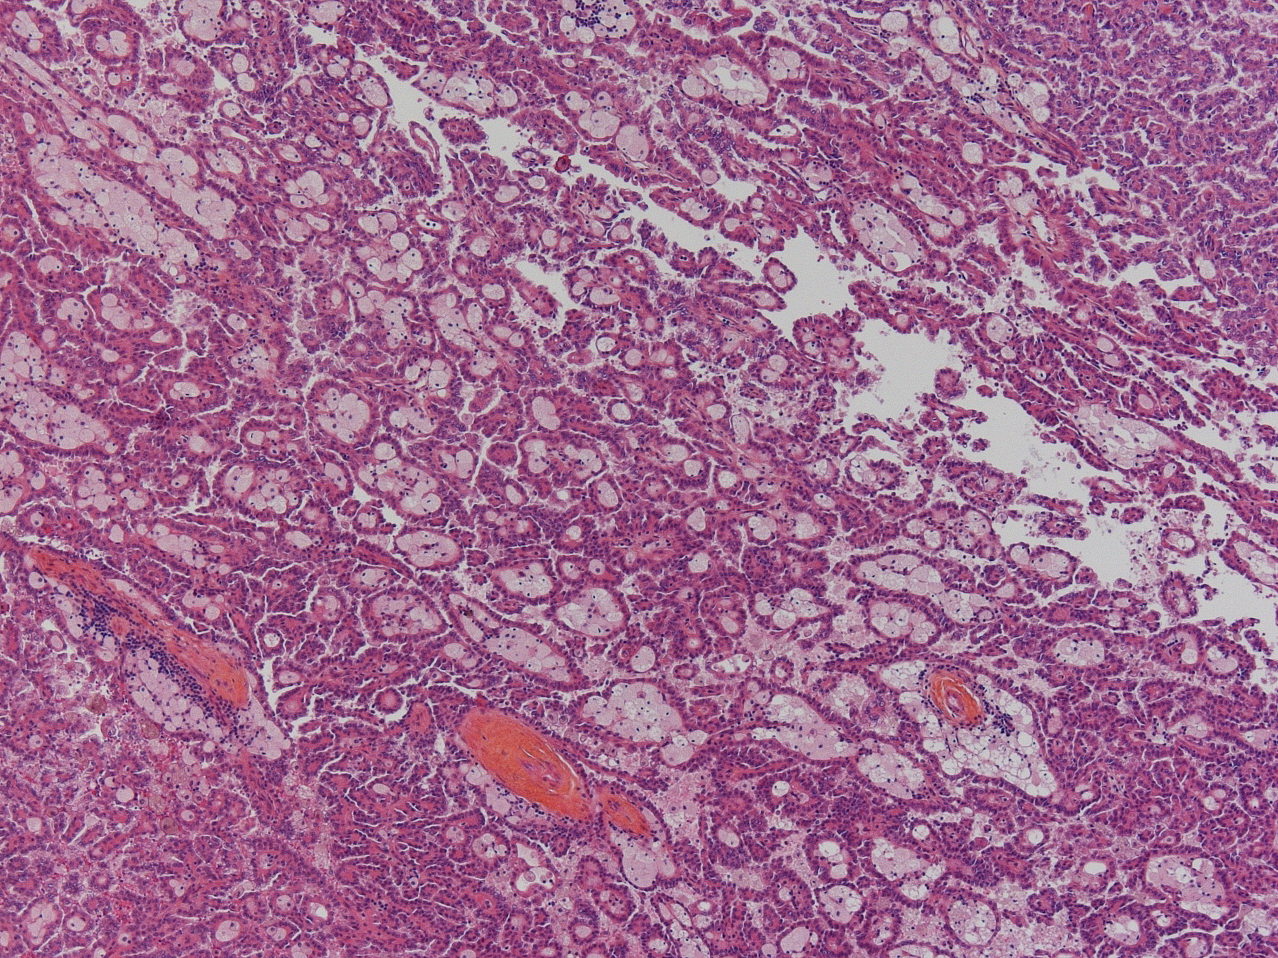

Renal tumor grading

Case ID: 928